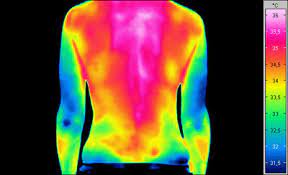

Vasculaire doorbloeding, spieren bij mens en dier en nachtzicht toepassingen.